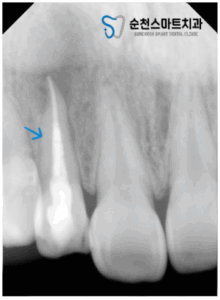

25.08.07

신경치료를 마무리한 모습입니다.

치아 내부의 근관하얀 약물

꼼꼼하게 채워진 것을 알 수 있는데요.

그렇지만,

워낙 뿌리끝 염증이 심한 상태였기 때문에

경과를 주기적으로 확인하며

일시적으로 불편한 느낌이 드실 수 있다는 점과

너무 단단한 음식을 앞니로 드시는 것을 피하고,

이후 크라운 보철물을 제작하는 것으로

장기계획을 세웠드렸습니다.